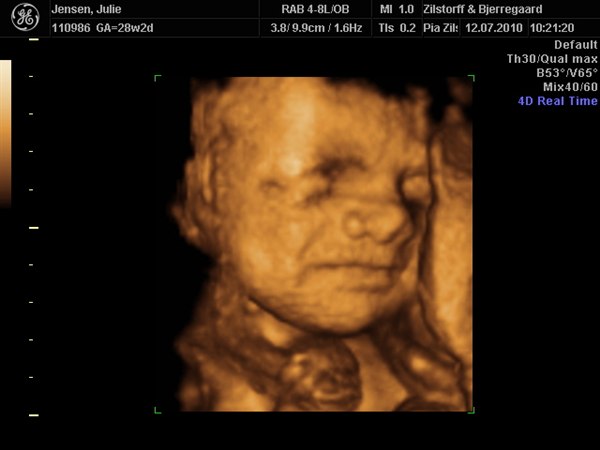

smilehuller og ligner helt sikkert Viktor

Kan slet ikke komme mig over hvor fantastisk det er at se det lille menneske inden i en

Vedhæftede fotos (klik for at se i fuld størrelse)